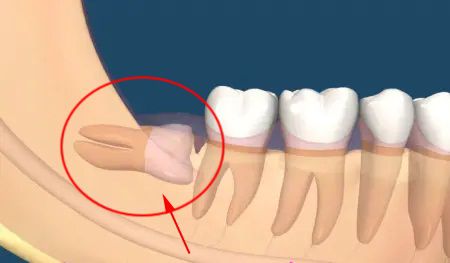

很多人不知道,智牙這樣拔才科學!2021-07-30

很多人不知道,智牙這樣拔才科學[ 查看詳細 ]

很多人不知道,智牙這樣拔才科學!2021-07-30

很多人不知道,智牙這樣拔才科學[ 查看詳細 ]